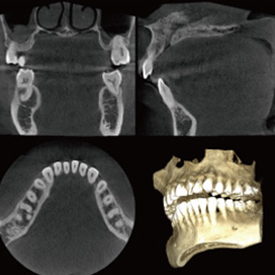

精度が高い診査・診断&安心・安全な治療歯科用CT- Computer Tomograghy -

CTとはComputer Tomograghyの略で、日本語ではコンピューター断層撮影と訳されます。 これは、X線とコンピューターによって、歯や骨の位置や形態などを3D画像で立体的に撮影するための医療機器です。

血管や神経の位置を立体的に把握し、骨量、骨密度を正確に確認できるため、インプラント治療の際にはCTによる診査・診断が必須となっています。

多くの歯科医院では、CTを撮影するために外部のスキャニングセンターへ撮影に出向く必要がありますが、当クリニックでは院内にCTを設置しているため、レントゲンと同じように院内で撮影し、即座に診ることができます。